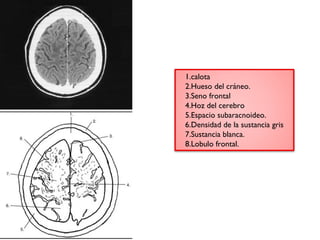

1.calota

2.Hueso del cráneo.

3.Seno frontal

4.Hoz del cerebro

5.Espacio subaracnoideo.

6.Densidad de la sustancia gris

7.Sustancia blanca.

8.Lobulo frontal.

1.Calota.

2.Seno frontal

3.calota

5.Hueso del craneo